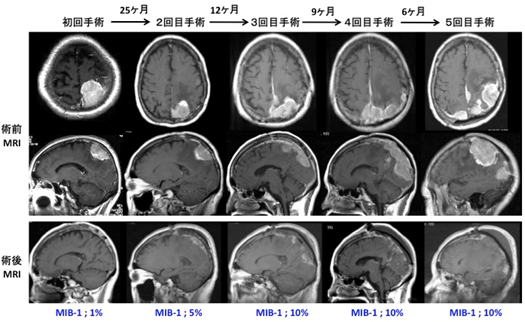

※ 基本的には髄膜腫は手術だけで治すことができる脳腫瘍ですが、約20%で悪性化することが知られています(当科もほぼ同じ頻度です)。当初良性髄膜腫にて全摘したにもかかわらず、その後10年越しで再発をきたし、計5回にわたり開頭腫瘍摘出術を行わざるを得なかった症例を経験しています。

(MIB-1とは腫瘍細胞の中で増殖活動が活発な細胞がどのくらい含まれているかを示しています。良性髄膜腫は概ね3~5%以下であり、悪性化すると10%以上になります。上記の症例は手術を重ねるたびにMIB-1の値が増加し、再手術までの期間が短縮していることがわかります。)